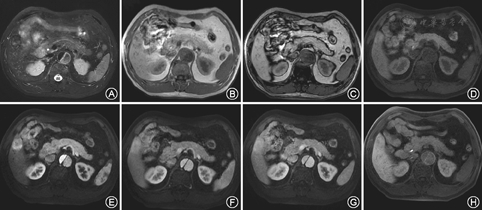

22个局灶性病变中:3个有脂肪变性(合并脂肪肝背景者仅1个);1个有出血(图1);7个有假包膜;动态三期增强扫描强化方式:12/22个渐进性持续强化;3/22个快进快出;7/22个快进慢出(图1)。5个>3 cm病灶无瘢痕;3个病灶肝实质有脂肪肝背景;1个病灶有肝硬化背景;20/22个病灶做特异性对比剂,20/20病灶摄取对比剂呈与肝实质呈等稍高信号。1例为弥漫性病灶,女性,有明显脂肪变性,无出血,无假包膜,增强方式快进慢出,有脂肪肝,无肝硬化背景,均摄取肝脏特异性对比剂。

Ferlicot等[7]研究表明,85%的不典型FNH存在病灶内脂肪。本研究发现3个病灶有脂肪变性(合并脂肪肝背景者仅1例),1例弥漫性病灶患者有脂肪肝背景,病灶内见脂肪变性改变。原因可能是临近的肝脏脂肪变性延伸进FNH病灶中[2],也可能是FNH出现自行退变(尤其是年龄大的患者中)[8]。另外,本研究的1/22个局灶性病变有病理证实的出血,这也可能是FNH退变造成的[9]。

本研究发现7/22个病灶有假包膜,这可能是临近受压的肝组织或伴炎性改变[6]。本研究中12/22个病变渐进性持续强化,7/12个病灶中有中央瘢痕存在。因此渐进性持续强化原因可能是病灶组织内含较多大的窦状扩张和较多放射性纤维分隔存在[9],延缓了对比剂在细胞外间隙中的扩散速度。